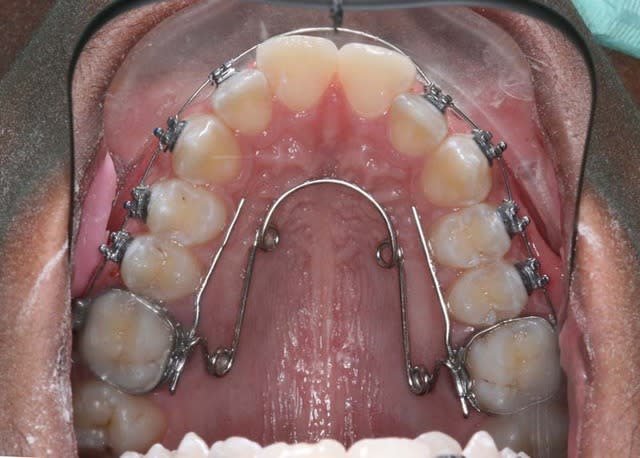

salut,

voici la mécanique mise en place pour ce cas et comment j’utilise (en friction faible, forces faibles) le fait que les Inc. Lat. soient bloquées en lingual pour le redressement des 3/4/5 tout en évitant la pro-version des Inc. centrales qui est Tjs. longue à rattraper et peut occasionner des rhizalyses

@+ Bjc.

mon arc (très peu puissant) est bloqué en 14, un peu en 12 et en 22

+ l’action du Q.H.

+ l’action de la lèvre Sup.

tu n’es pas obligé de croire, donc voici le résultat,

je viens de placer un arc 16*x16* austénitique, toujours pas inclus 11/21,

je vais d’abord appareiller le bas (sans inclure les 6) à la rentrée. pour encore laisser rentrer les centrales Sup. sous la pression de la levre